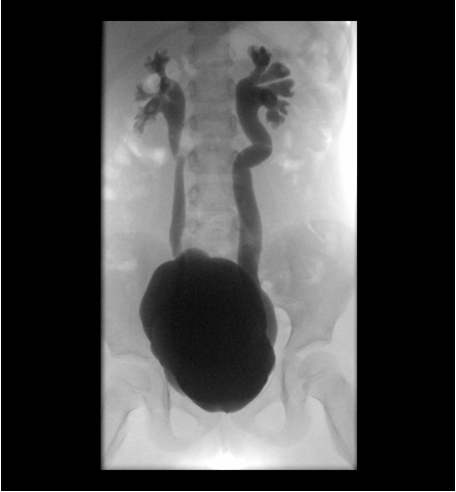

La Cistouretrografía Miccional Seriada permite, habiendo administrado contraste yodado a través de una sonda vesical que posteriormente se retira, valorar la capacidad vesical, la pared vesical, la existencia o no de reflujo vesicoureteral uni o bilateral y, una vez retirada la sonda vesical, valorar la uretra y descartar cualquier anomalía en el tracto urinario inferior. En este caso, ya que se habla de una paciente que ha tenido un reflujo vesicoureteral (en el cual las válvulas vesicoureterales son incompetentes) tratado con Sting (cirugía endoscópica antirreflujo) pero que se sospecha que ha recidivado, con esta técnica vamos a poder valorar la vejiga y ver si hay reflujo vesicoureteral y el grado de éste.